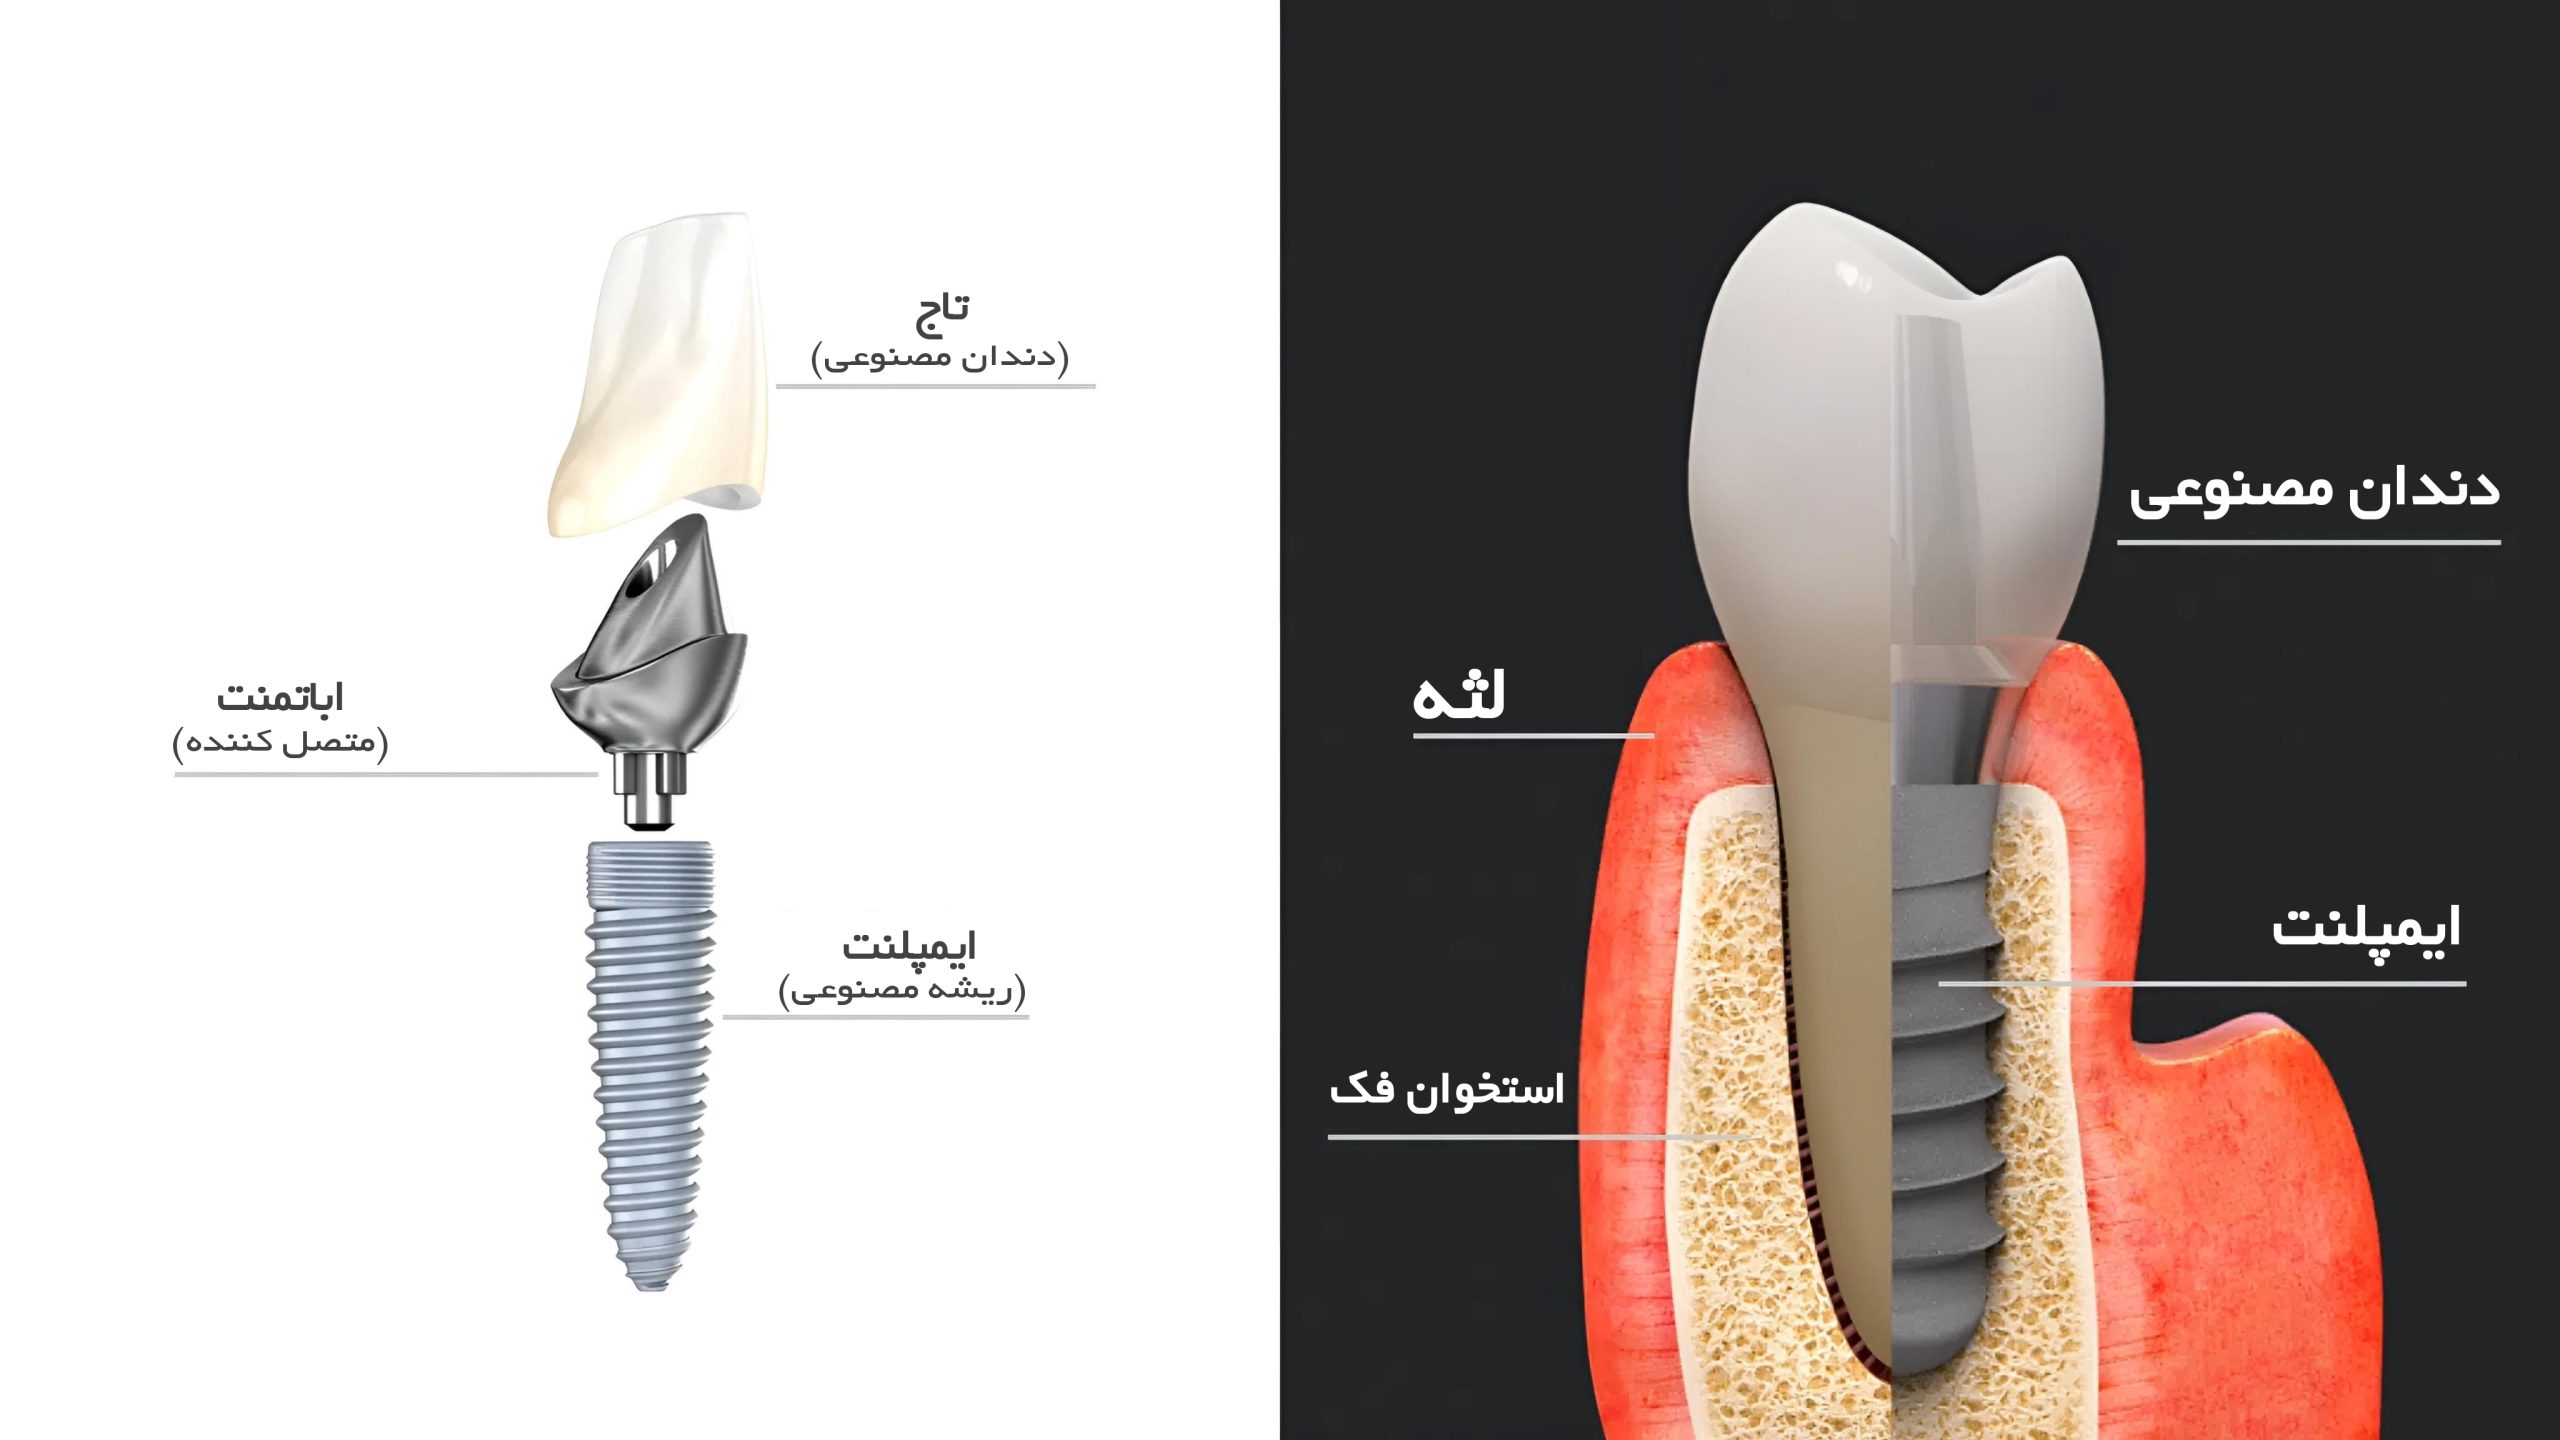

برخی از افراد به دلایل مختلف ممکن است دندانهای خود را از دست بدهند. همانطور که در تصویر بالا نشان داده شده، ایمپلنت دندان یا فیکسچر به اندازه ریشه دندان فرد، بهجای ریشه از دست رفته قرار میگیرد. فیکسچرها قطعاتی هستند که به اندازه دندان طبیعی ساخته میشوند و با دقت بالا طراحی میشوند تا بهطور کاملاً طبیعی به نظر برسند.

ایمپلنت دندان از دو قسمت اصلی تشکیل میشود فیکسچر (Fixture) و اباتمنت (Abutment). قسمتی که در داخل استخوان فک قرار میگیرد، فیکسچر نام دارد و قسمتی که بالای لثه قرار میگیرد، اباتمنت نامیده میشود. روی اباتمنت، پروتز یا روکش ایمپلنت نصب میشود. پایه ایمپلنت معمولاً از تیتانیوم ساخته میشود زیرا تیتانیوم بهدلیل سازگاری بسیار خوب با استخوان فک، از ایجاد مشکلاتی مانند لغزش، سر و صدا یا آسیب به استخوان جلوگیری میکند.